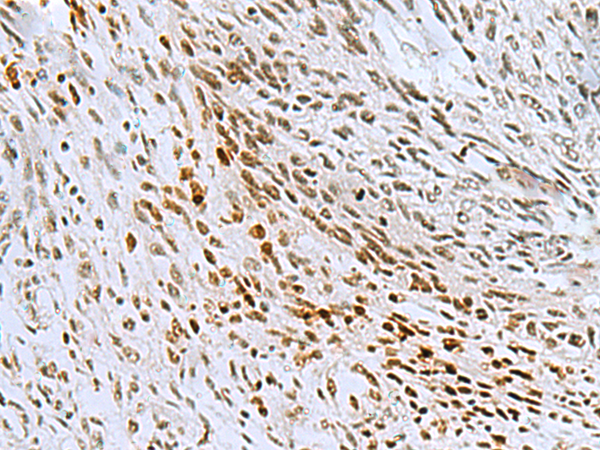

分类: 科研抗体货号: P03292别名:应用: IHC反应种属: Human, Mouse, Rat